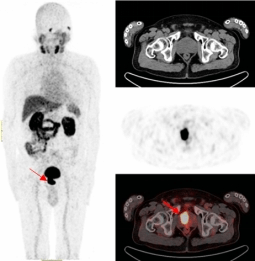

一名69岁的男性患者因常规体检发现血PSA明显升高后,辗转多家医疗机构,复查两次血PSA、一次盆腔MR平扫+增强,两次前列腺穿刺活检,均被确诊为前列腺结节性增生。

既无肉眼血尿,又无排尿异常,更没有腰酸背痛,但多次血PSA结果异常。患者遂来到p站

附属医院核医学诊疗中心接受了68Ga-PSMA-PET/CT检查,结果显示前列腺的确存在良性增生,在结合PET/CT核素影像诊断进行靶向穿刺精准定位后,最终确诊为前列腺腺癌。

前列腺一旦发生癌变就会特异性表达前列腺特异性膜抗原(PSMA),其作为近年来国际上最新的靶向前列腺癌的分子靶点,68Ga-PSMA PET/CT对于前列腺癌的检测在敏感性、特异性、阳性检出率上均高于传统检查手段,对原发灶和转移灶检出率可达到95%,对前列腺癌精准地早期发现、早期诊断,让患者少走弯路。